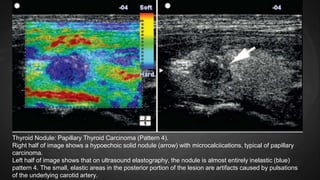

Thyroid Nodule: Papillary Thyroid Carcinoma (Pattern 3).

(A) Conventional longitudinal B-mode sonogram demonstrates a hypoechoic papillary carcinoma with

irregular, poorly denied margins (arrow).

(B) Ultrasound elastography shows a predominantly inelastic (blue) pattern with a few small, elastic

(green) areas in the posterior portion.